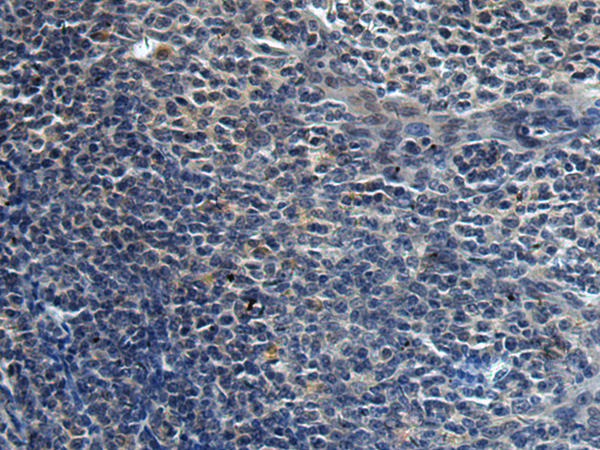

分类: 科研抗体货号: P10402别名: Dgt6; FAM29A应用: IHC反应种属: Human